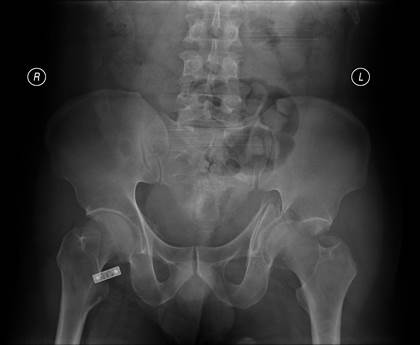

病例一:左髋臼骨折、骶髂关节脱位,Tile C3分型,术前X线